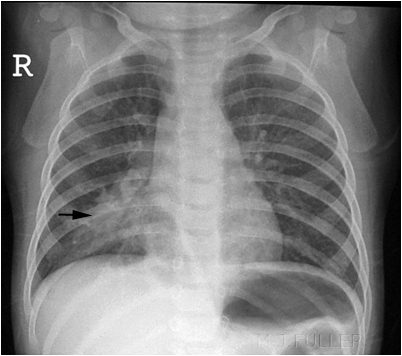

Example 1

Take a look at the following example. Let us go through how we would systematically analyse this and the diagnosis.

Analysis and Diagnosis

D – This is a Chest X-Ray taken on ….., of the following patient….. Is there a previous CXR to compare to

R – Commenting first on the quality, it is not rotated, there is adequate inspiration, the projection is posterior-anterior and it is adequately exposed as I can see the vertebral bodies clearly

“On initial inspection, there appears to be increased consolidation in the right middle lobe, but I will proceed to go through it systematically.”

A – Starting with the airways, the trachea is not deviated, and the carina is visible.

B – The pleural markings go all the way to the costal margin so there is no evidence of a pneumothorax. Going through the lung zones, there is increased opacification in the right middle lobe compared to the left, with obscuring of the right border of the heart. There is an air bronchogram present which is suggestive of middle love consolidation.

C – The heart is not enlarged. There is loss of the silhouette sign in the right border of the heart.

D – The hemidiaphragms are clearly visible and there is no blunting of the costophrenic angles. There is no free air under the diaphragm.

E – There are no foreign objects or bone fractures.

There is no abnormality in the review areas, including the apices, behind the lung.

Diagnosis

Right Middle Lobe Pneumonia